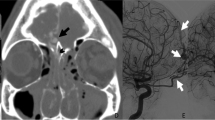

Table 4 summarizes the frequency of the various causes of classification differences. Figure 3 illustrates each etiological category.

Examples of possible microbleeds at t1 classified differently at t2. a Pathophysiological difference (disappearance); b possible pathophysiological difference, with slightly decreased signal intensity and increased blooming at t2, which may be caused by a technical difference between the scans or by a pathophysiological change; c equivocal classification, especially at t1 this configuration can as well be classified as a possible microbleed as as a continuation of the blood vessel medial to it; d misinterpreted otherwise: this subarachnoid blood was mistaken for a possible microbleed at t1; e misregistration or missegmentation: at both time-points, this possible microbleed was segmented too small; the segmentations did not overlap, resulting in a false mismatch in the automatic comparison step; f artifact hampering the interpretation (susceptibility at air-tissue interface); g artifact precluding evaluation at t2 (susceptibility at air-tissue interface). Images are axial images. Arrows point to the microbleeds discussed. In e, the automatic segmentation resulted in the closed curves. t1: 3 (2–5) weeks after TBI, t2: 26 (25–28) weeks after TBI